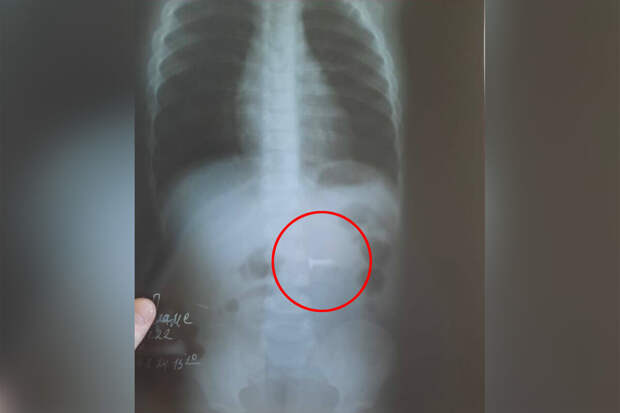

В медицинское учреждение был доставлен годовалый ребенок с подозрением на инородное тело в желудке. По словам родителей, сын остался без присмотра, нашел в квартире саморез длиной полтора сантиметра и проглотил его.

В ходе обследования инородный предмет обнаружили в желудке, врачам удалось извлечь саморез из двенадцатиперстной кишки маленького пациента.